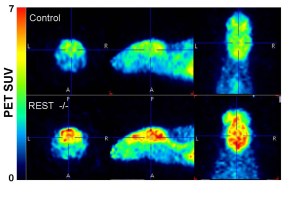

Scientists pinpoint neural activity’s role in human longevity

The brain’s neural activity, long implicated in disorders ranging from dementia to epilepsy, also plays a role in human aging and life span, according to research led by scientists in the Blavatnik Institute.